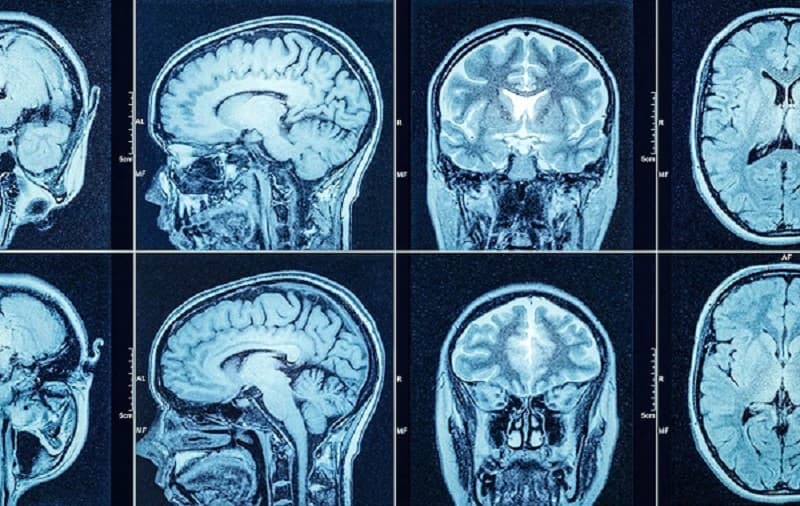

Chụp CT đầu giúp bác sĩ chẩn đoán nhanh chóng và chính xác các vấn đề liên quan đến não bộ